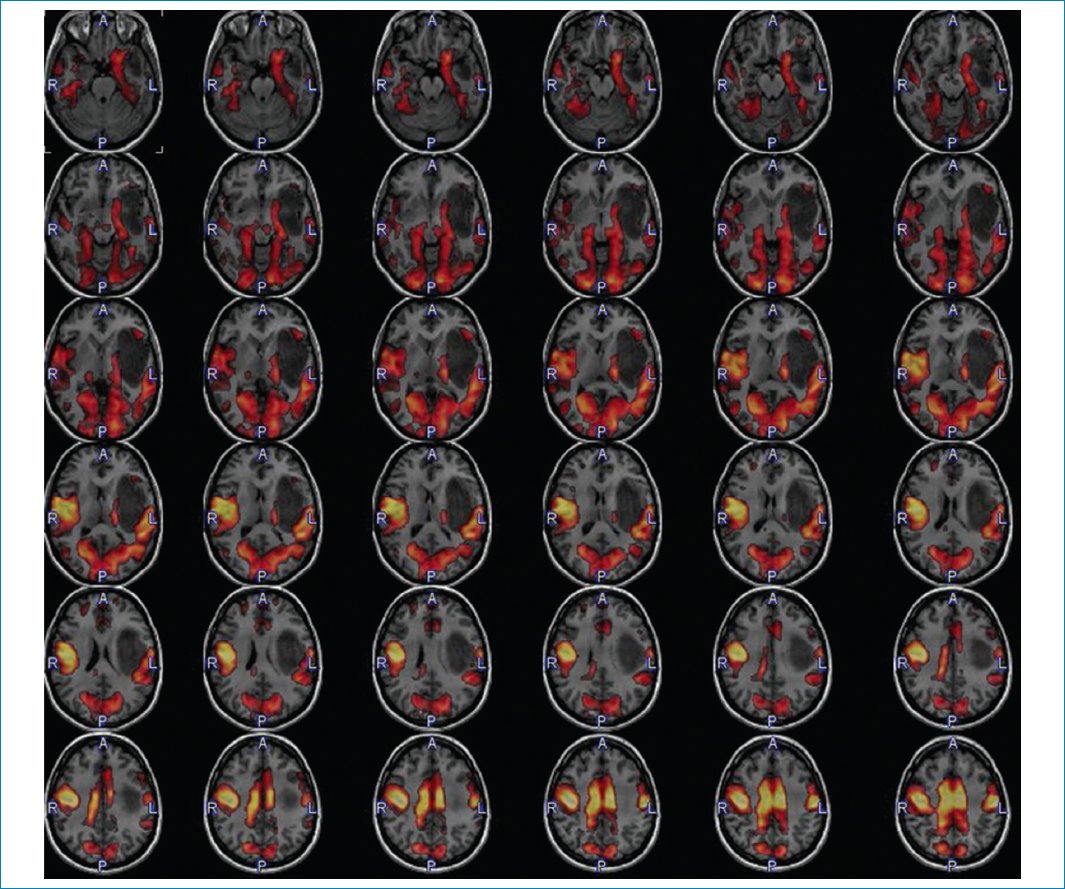

Los síntomas de la paciente pueden ser correlacionados con su lesión extendida al área central izquierda, lo cual es muy bien graficado en el estudio de RM en estado de reposo11,12 (Fig. 8).

Figura 8. Relación de la masa con las proyecciones sensitivomotoras. RM funcional en estado de reposo.